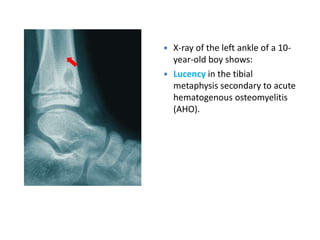

X-Ray

• 1st 10 days Show No Abnormality .

Only after two or three weeks do visible changes appear, and they may never do

so if efficient treatment is started very early.

• By the end of the 2nd Week signs of rarefaction of Metaphysis and

New Bone Formation. Then sigs of healing

• Soft-tissue edema at 3-5 days after infection.

• Bony changes are not evident for 14-21 days:

– Early radiographic signs of rarefraction (thining of bony tissue

sufficient to cause decreased density of bone) of the

metaphysis and new bone formation outlining the raised

periosteum

– Sclerosis and thickening of the bone cortex at healing

• Approximately 40-50% focal bone loss is necessary to cause

detectable lucency on plain films; a negative X-Ray does not

exclude osteomyelitis

 X-ray of the left ankle of a 10-

year-old boy shows:

 Lucency in the tibial

metaphysis secondary to acute

hematogenous osteomyelitis

(AHO).

 X-ray ofthe left ankle of a 10- year-old boy shows:  Lucency in the tibial metaphysis secondary to acute hematogenous osteomyelitis (AHO).